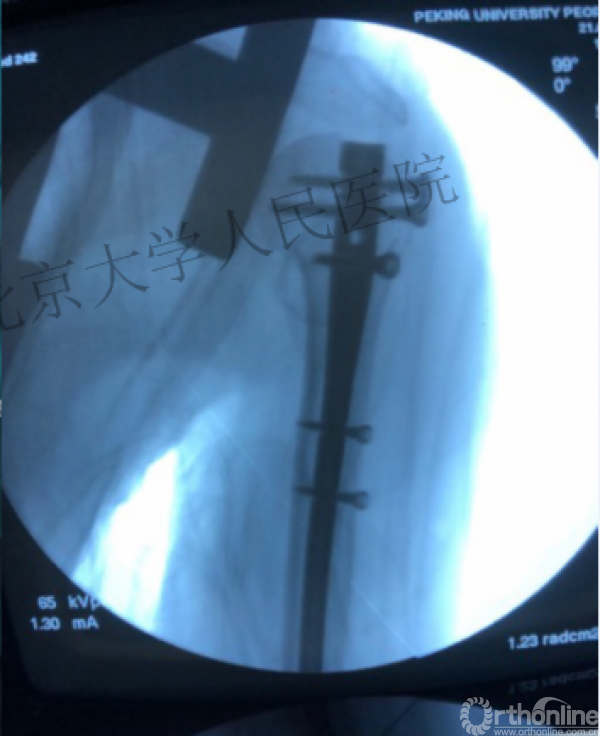

术中片

透视肱骨头正位、侧位确定进针点

复位良好的标准:颈干角:135°,大结节与肱骨头距离:8mm